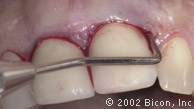

Вид спустя десять недель после установки имплантантов

Установка двух 3.0mm Impression Post

Снятие слепка и подбор цвета

Установка временной и изготовление постоянной конструкции